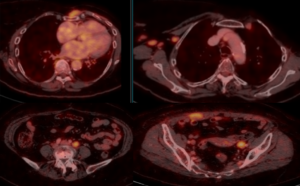

52 year old lady with right breast mass of recent onset.

What is the mass?

Clue: She is IDDM since 15 years